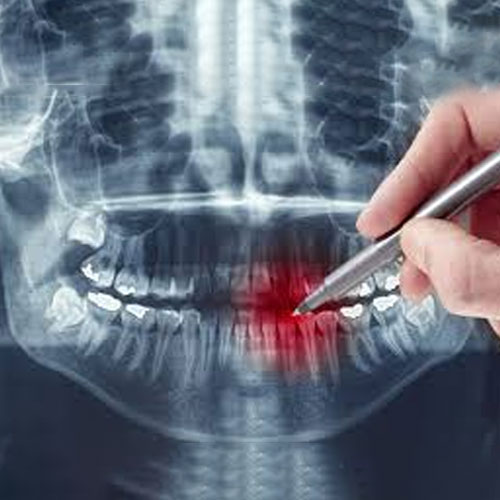

Consultation

The first step involves Dr Pierluca thoroughly examining the affected tooth, including X-rays, to determine the extent of the damage or infection. This helps him plan the best approach for your root canal treatment.